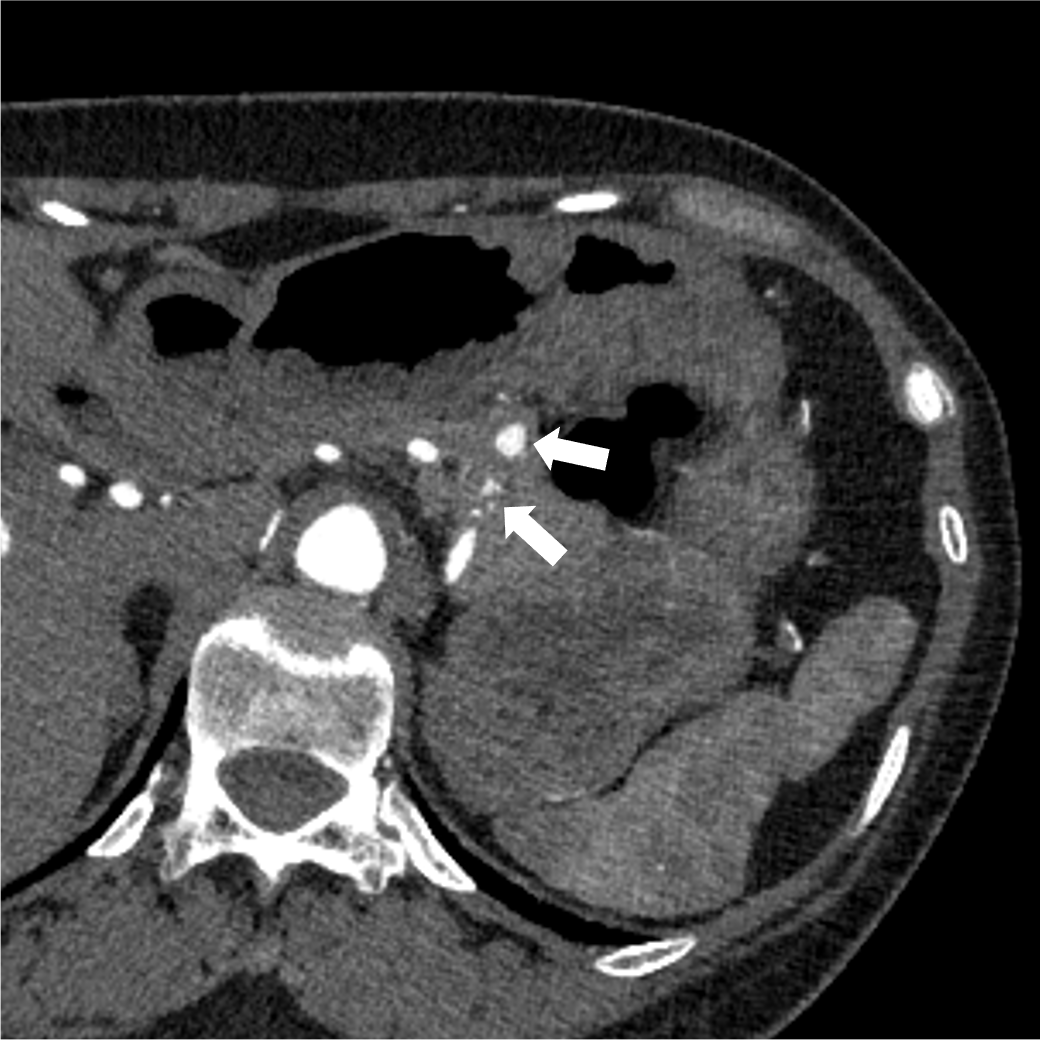

検診で指摘された肺病変のCT精査にて、肺の動静脈奇形(AVM)と診断された。精査および加療目的で当院に紹介され、術前精査のための造影CTを施行した。造影CTにて、膵尾部にAVMを認めた。その後、肺AVMに対するコイル塞栓術が施行され、その際に膵AVMも血管造影にて精査が行われた。膵AVMによる症状はなく経過観察とされ、外来にて定期的にフォローアップされている。

オスラー病(遺伝性出血性毛細血管拡張症、HHT)は、全身の血管に異常を生じる、常染色体優性遺伝の遺伝性疾患であり、特に肺・脳・肝臓・消化管などの動静脈奇形(AVM)や、鼻出血、口・指・鼻などの毛細血管拡張を生じることで知られる。膵臓にも30-60%の患者に血管病変を生じるとされ、その約2/3が毛細血管拡張、約1/3がAVMと言われている。

単純CTでは膵臓の異常血管の描出は困難であり、造影CTは診断において重要である。膵臓のAVMにおいては、(1)拡張・蛇行した供血路、排血路といった異常血管の描出や、(2)動脈相で門脈系の血管の早期造影効果が認められ、診断のポイントとなる。造影CTは血管造影と比較して侵襲性が低く、膵実質の全体の評価にも適しているため、精査のみならず、フォローアップにも用いやすい。